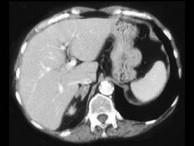

问题 女,42岁,夜尿增多伴高血压,实验室检查:血和尿醛固酮水平增加,请结合图像,选择最佳答案 ( )

选项 A、双侧肾上腺转移瘤 B、双侧肾上腺淋巴瘤 C、双侧肾上腺腺瘤 D、双侧肾上腺未见异常 E、双侧肾上腺增生

答案 E